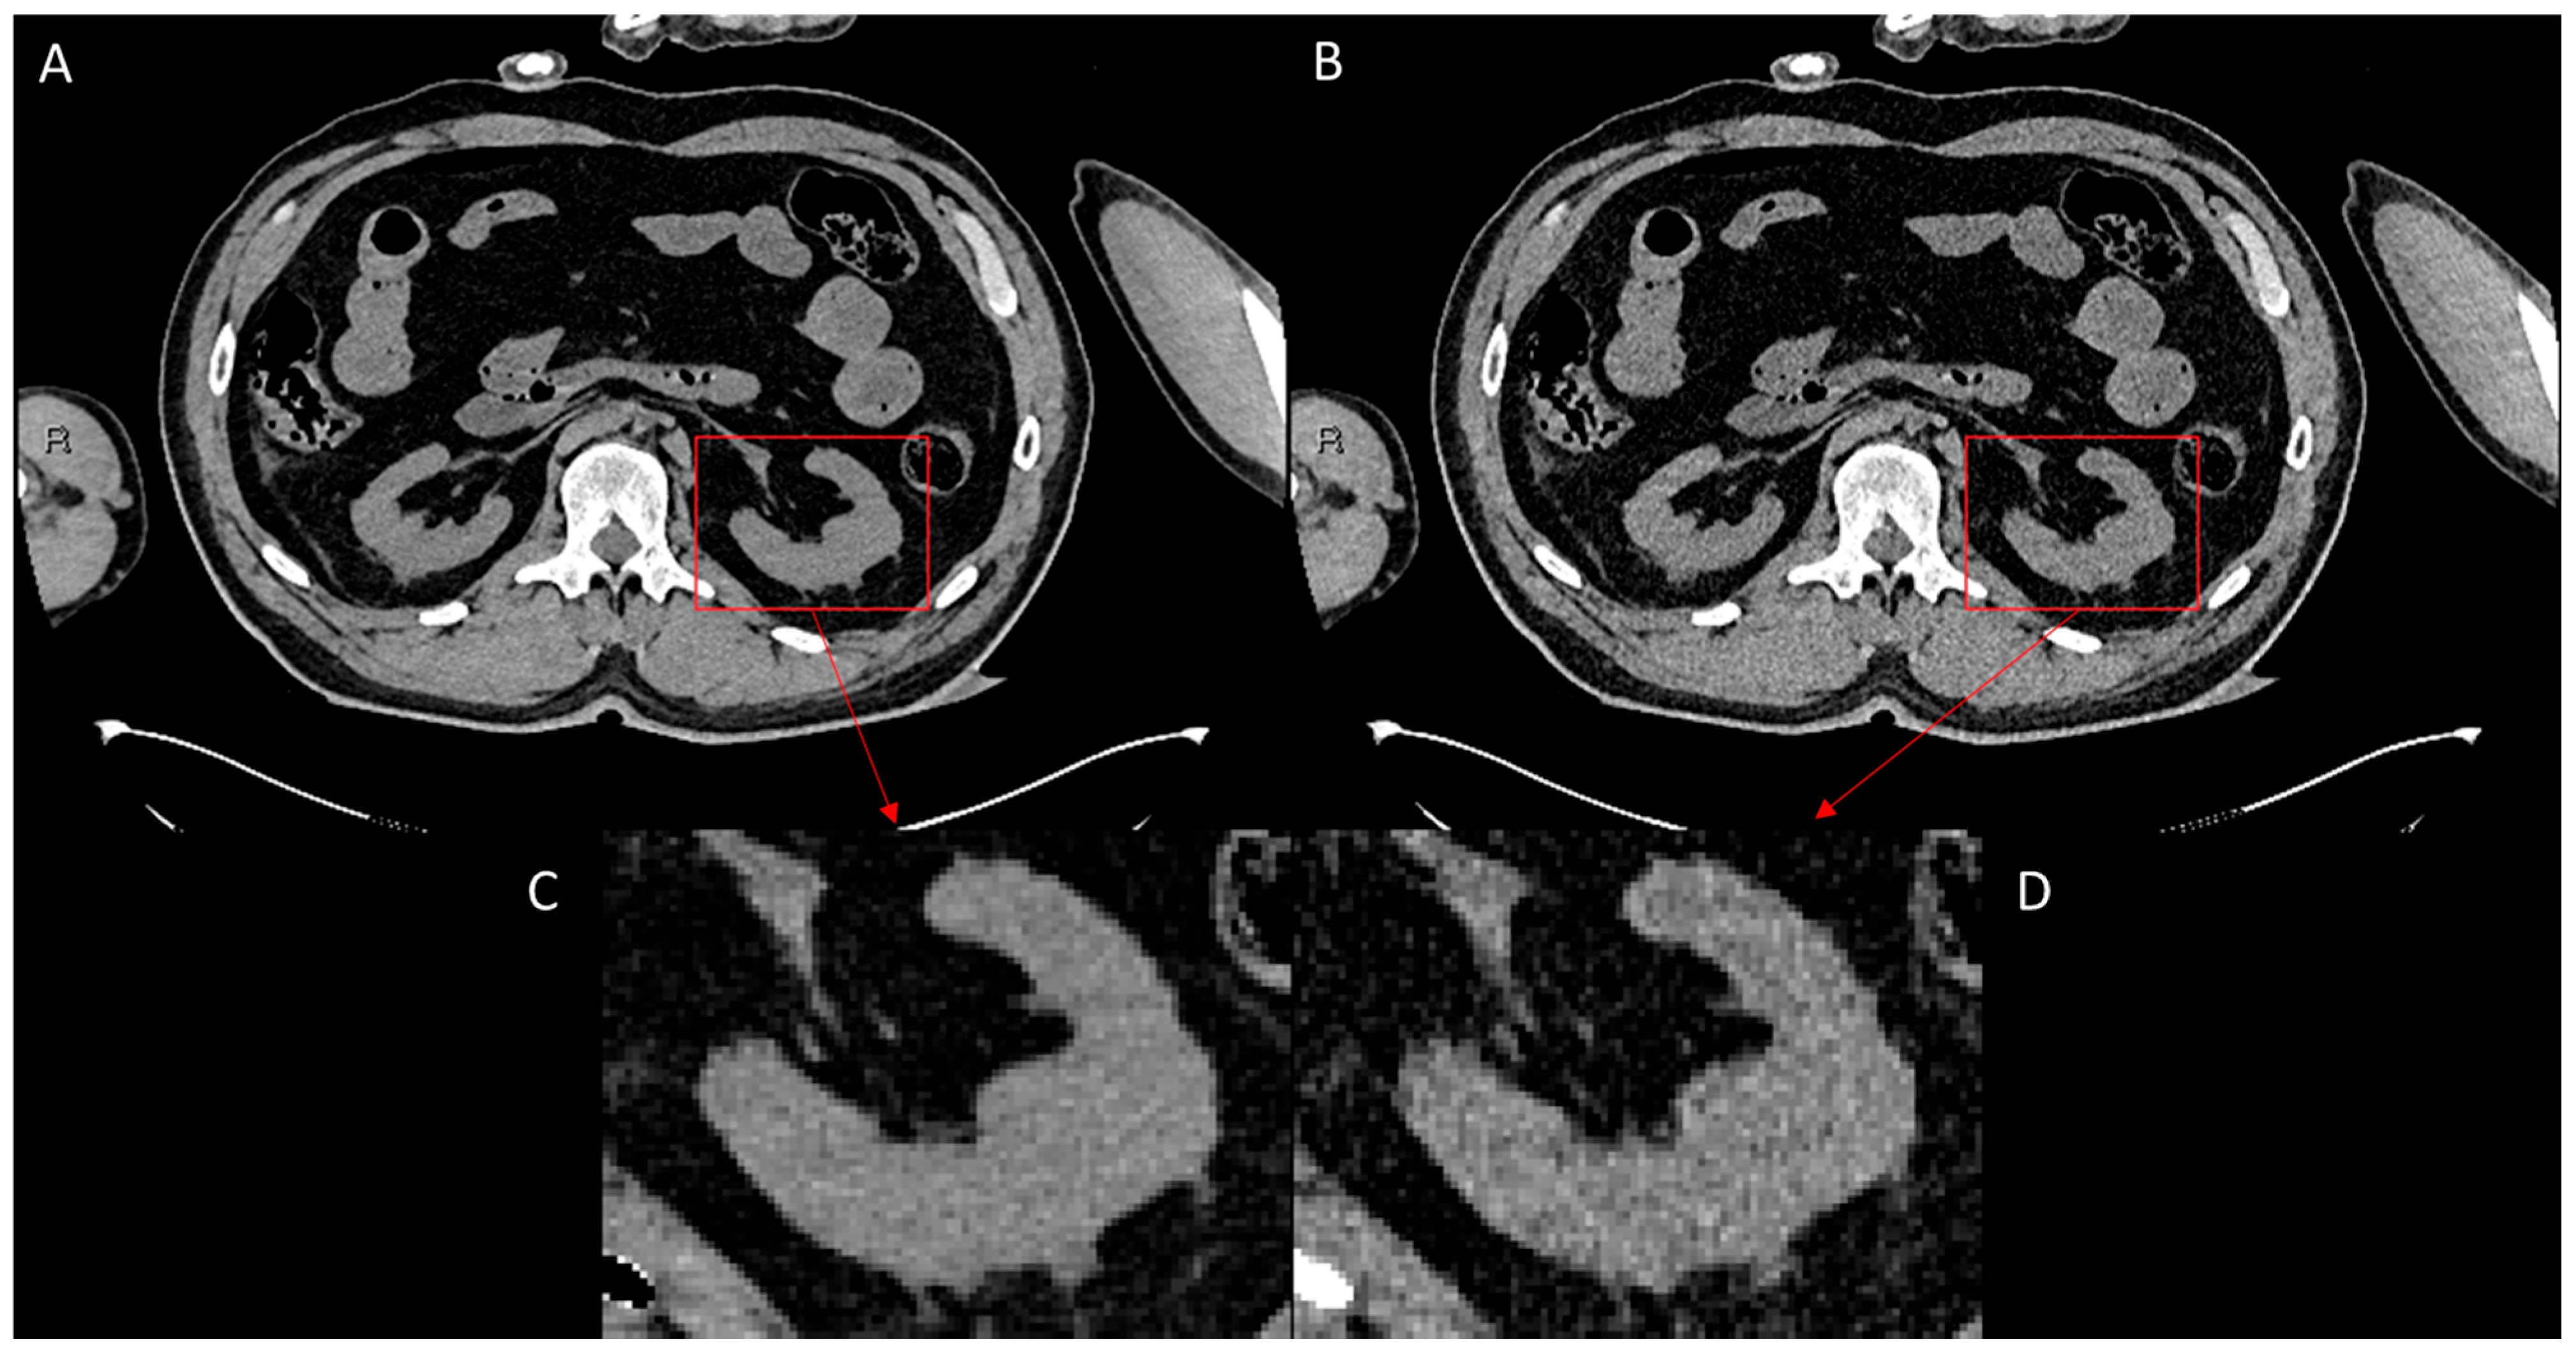

To evaluate the performance of ErisNet on the test set, we implemented a comprehensive protocol [] to assess the model’s efficacy in noise reduction and its subsequent impact on CT image quality. The following results indicate ErisNet’s performance across various metrics, demonstrating a significant reduction in noise compared with the original LQ images (Figure 4).

Figure 4.

Comparison of CT image quality before and after processing with ErisNet, with detailed enlargements. (A) Image processed with ErisNet, showing significantly reduced noise levels and increased sharpness. (B) Corresponding low-dose image, used as input for ErisNet, showing increased noise. (C) Magnified view of a specific region of interest (red box), the left kidney, in image (A), highlighting the noise reduction and detail preservation achieved by ErisNet. (D) Magnified view of the same region of interest (red box) of the left kidney in image (B), illustrating the significant noise present in the original low-dose image before processing.